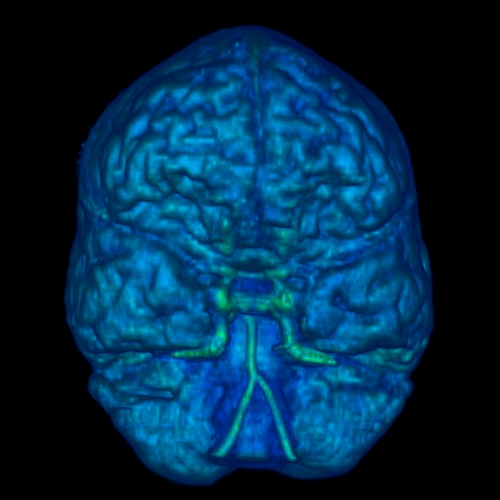

Three dimensional reconstructions of the scalp and neural tissue were created using the software AVS by stacking, transforming and rendering the MR data using ray tracing. Here are images of the reconstructed scalp and neural tissue.

Scalp Reconstruction Brain Reconstruction Brain Reconstruction Brain Reconstruction

Scalp Posterior View of Neural Tissue Anterior View of Neural Tissue Lateral Right View of Neural Tissue

Small blobs appearing in the MR slices and in the reconstructed scalp image are from fish-oil capsules which were used as markers to establish a transformation matrix for the MRI data and create a co-ordinate system.

Computer animations of the scalp and brain rotating were made using the software AVS. These were created using isosurfaces, rather than ray-tracings. Here is a movie of the scalp rotating (QuickTime format, 11.0Mb or AVI format, 0.7Mb) and a movie of the brain rotating (QuickTime format, 6.6Mb).